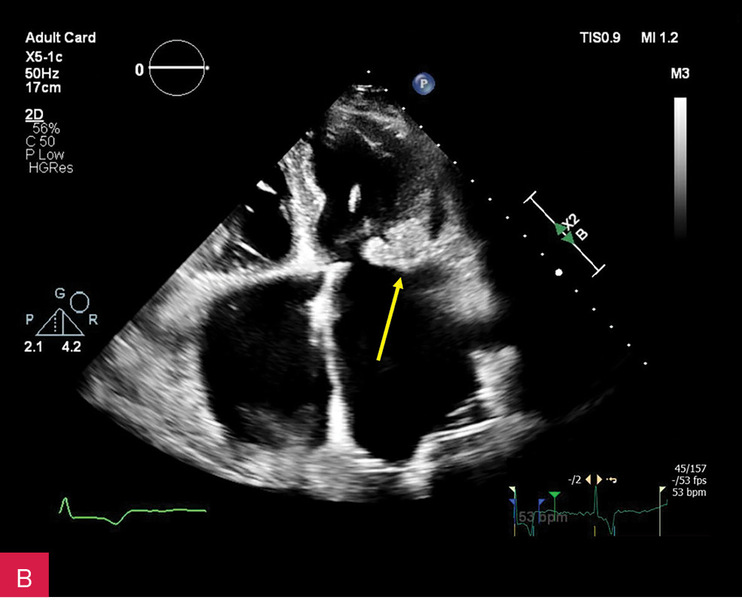

Rycina 2A, B. Zmiana u podstawy tylnego płatka mitralnego, obejmująca jego nasadę, a także fragment mięśnia ściany dolno-bocznej lewej komory w projekcji przymostkowej w osi długiej LAX (A) oraz w projekcji zmodyfikowanej, w której lepiej uwidoczniono hiperechogeniczną uwapnioną otoczkę zmiany oraz powodowany przez nią cień akustyczny (B)